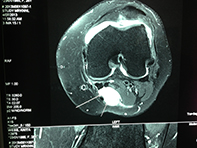

MRI Of Lateral Parameniscal Cyst

Bony Bruising Pattern ACL Tear